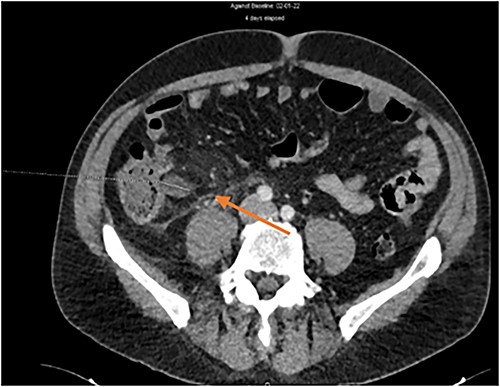

Abdominal computed tomography findings were compatible with uncomplicated acute appendicitis (Fig. 1).

Abdominal CT scan. Diagnosis of uncomplicated acute appendicitis.